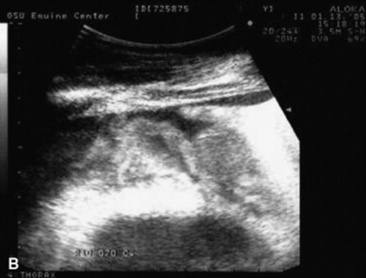

C. immitis is a soil saprophyte that grows in semiarid areas with sandy, alkaline soils.375 Inhaled arthroconidia enlarge to form nonbudding spherules, which incite an inflammatory reaction in the lungs and lymph nodes.375 Horses have weight loss, fever, abdominal pain, and signs of respiratory disease (Fig. 31-26). Localized, recurring nasal granulomas also have been reported.376 Diffuse infections with granulomas in the lungs, liver, kidney, or spleen carry a grave prognosis.375 Przewalskii horses may be more susceptible.377

image image image

Fig. 31-26 A, Coccidiomycosis in a quarter horse mare with severe weight loss after a 3-month period in Arizona and Colorado. Ultrasound image of free (B) pleural fluid and (C) abdominal fluid.

Courtesy Jamie Murphy, Califon, NJ.

C. immitis is difficult to culture, and spherules may not be observed histologically from antemortem lung biopsies. However, serology is very useful to diagnose infection, and decreasing titers are associated with clinical improvement.332,375 Serum antibodies are detected rarely in healthy horses.378 Antifungal agents successful in treatment of infected horses include itraconazole and fluconazole.332,379